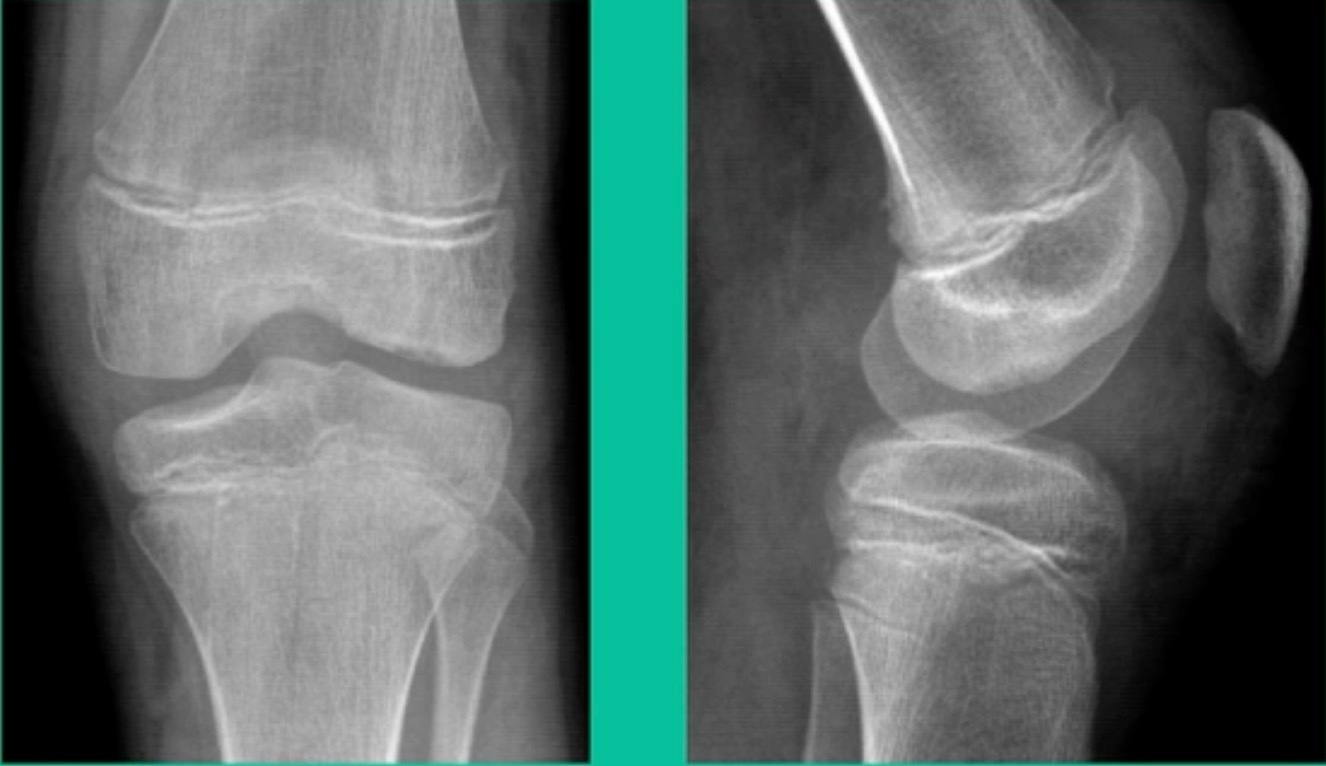

As a medical student or a resident, you’re taking boards: What’s the most common location of OCD? The lateral aspect of the medial femoral condyle. Second, the lateral femoral condyle. Lesions in the trochlea are third, followed by the patella. Then, every once in a while, you’ll see one involving the tibial plateau. And I’ve seen all of these. The average age is around 12 to 20 years old. Males get it more frequently. But we do see OCD in other places, like the ankle; females more commonly present than males. They tend to sprain their ankles more. Maybe there’s association. Males more than females in the capitellum, and that’s because we tend to see it in our throwers, followed by our gymnasts. There are theories that associate repetitive microtrauma, genetics , obesity, and ischemia with a predisposition to OCD lesions. Early on, patients will say very non-specific, vague complaints. Then they get progressive symptoms, and then they falter on with joint-specific symptoms like mechanical loading and things like that that cause pain.

Now a couple of quick cases. This is juvenile OCD. This is the first series of three or four, just juveniles. 14-year-old, intermittent knee pain, lateral femoral condyle OCD (Figure 1).

This is an 11-year-old. Left knee lateral knee pain. Effusions, the same type of classic findings (Figure 3)

Another case example. 14-year-old male tennis player, 10 months of knee pain (Figure 7A).

Now, we’ll shift to the adult. This is a 27-year-old. Right knee swelling, activity-related, and classic failed nonsurgical treatment on the lateral side of the knee.

43-Year-Old, symptomatic medial femoral condyle.

This is an 18-year-old with a lateral femoral condyle OCD: